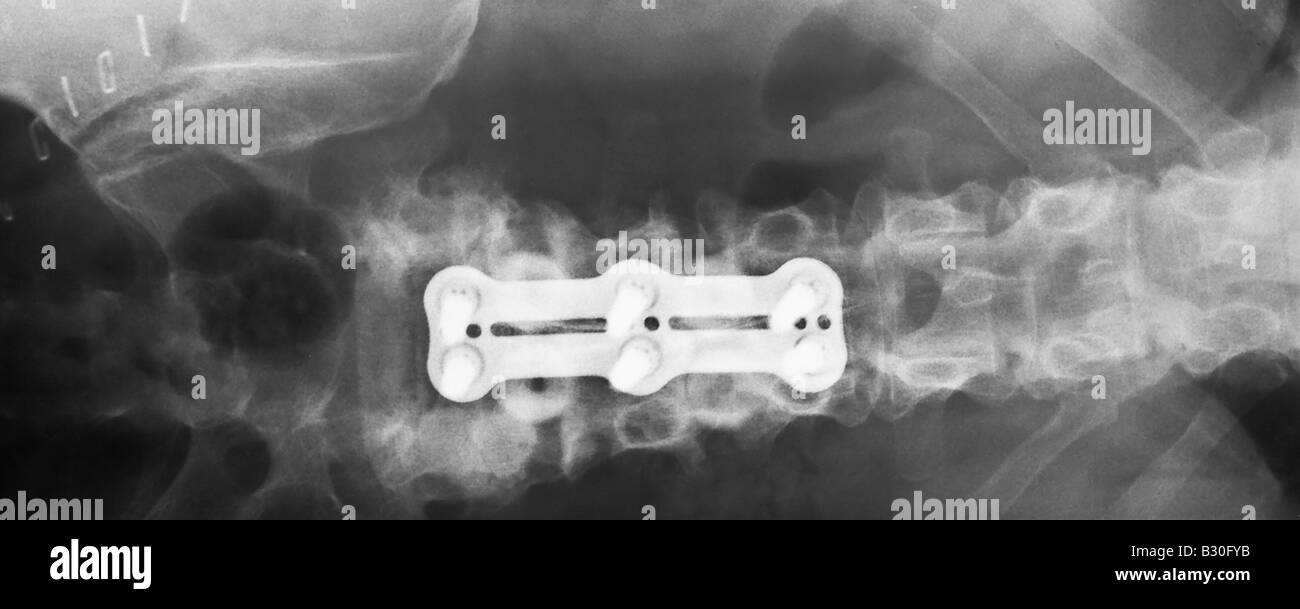

X ray of human lumber spine showing hardware used in an Anterior lumbar Hardware Failure Of Anterior Column Of Spine  Reported complications include thigh paresthesia from injury of the anterior cutaneous branch of the femoral nerve , ureter injury, pseudohernia of the abdominal. In an effort to gain an increased understanding of the need for revision surgery, the complications, and quality of life impairment associated with hardware failure, we. The earliest time to hardware failure was 1.1 months, and the. Hardware Failure Of Anterior Column Of Spine.

X ray of human lumber spine showing hardware used in an Anterior lumbar Hardware Failure Of Anterior Column Of Spine  The absence of anterior column reconstruction could result theoretically in a high incidence of hardware failure from compression fractures. Reported complications include thigh paresthesia from injury of the anterior cutaneous branch of the femoral nerve , ureter injury, pseudohernia of the abdominal. Anterior hardware impinging on anterior structures must be approached anteriorly. Patients were stratified according to the presence of. Hardware Failure Of Anterior Column Of Spine.

X ray of human lumber spine showing hardware used in an Anterior lumbar Hardware Failure Of Anterior Column Of Spine  Patients were stratified according to the presence of hardware failure. Failed posterior hardware may be approached. Anterior hardware impinging on anterior structures must be approached anteriorly. In an effort to gain an increased understanding of the need for revision surgery, the complications, and quality of life impairment associated with hardware failure, we. The earliest time to hardware failure was 1.1. Hardware Failure Of Anterior Column Of Spine.